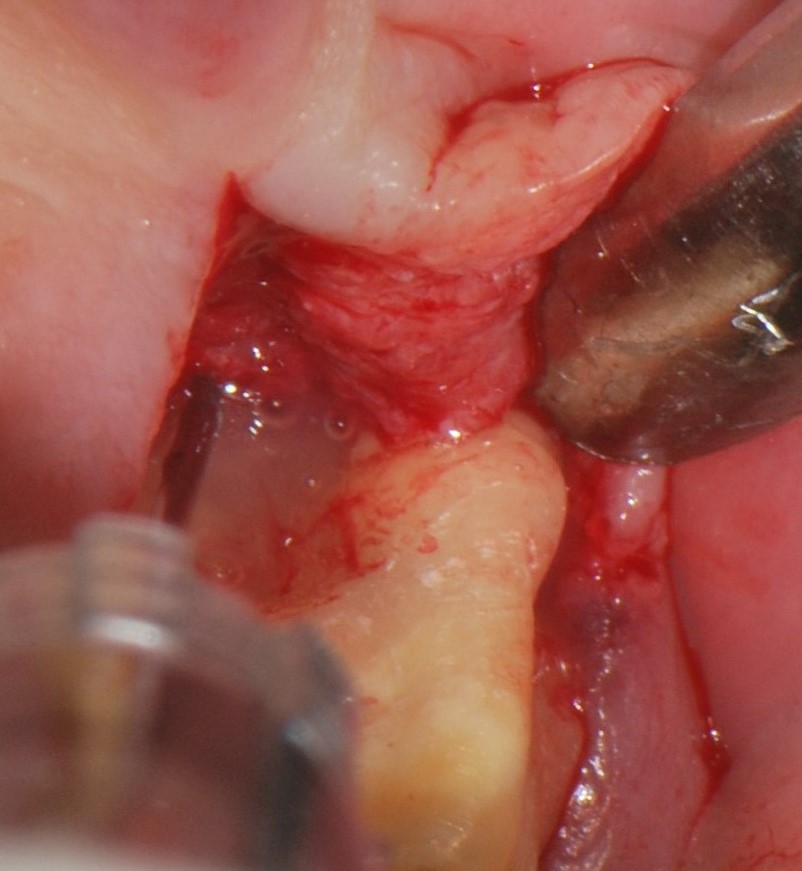

04/06 - Flap elevation by a midcrestal incision and application of Straumann® Emdogain® to the defect site.

Treatment of a periodontal bone defect adjacent to an edentulous site using Straumann® Emdogain® - Prof. Dr. P. Windisch